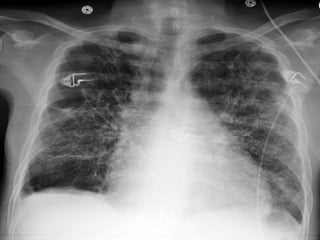

may appear nearly identical .Chest x-ray or CT scan

of the lungs can reveal haracteristic abnormalities.

aspergillosis diagnosed •Samples ofsputum, blood, or affected tissue can be cultured in the laboratory to grow aspergillus. •The fungus may be visible under a microscope in biopsies of affected tissue. Special stains for fungus may be needed, but other fungi may appear nearly identical .Chest x-ray or CT scan of the lungs can reveal haracteristic abnormalities. •A newer antigen-based test is available to detect evidence of invasive aspergillosis in the blood. However, the accuracy of this test appears to be variable.